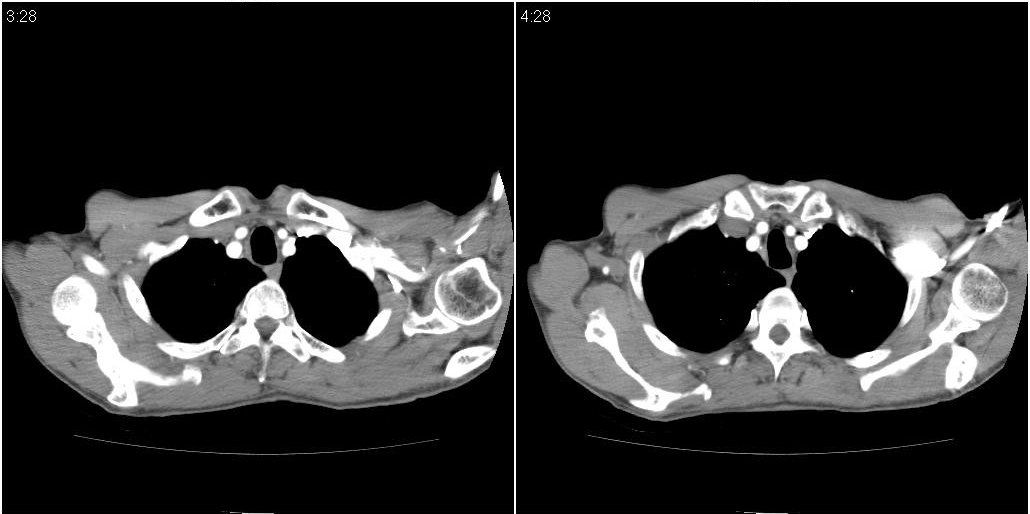

以下是ct检查的情况:

标题: ct增强: